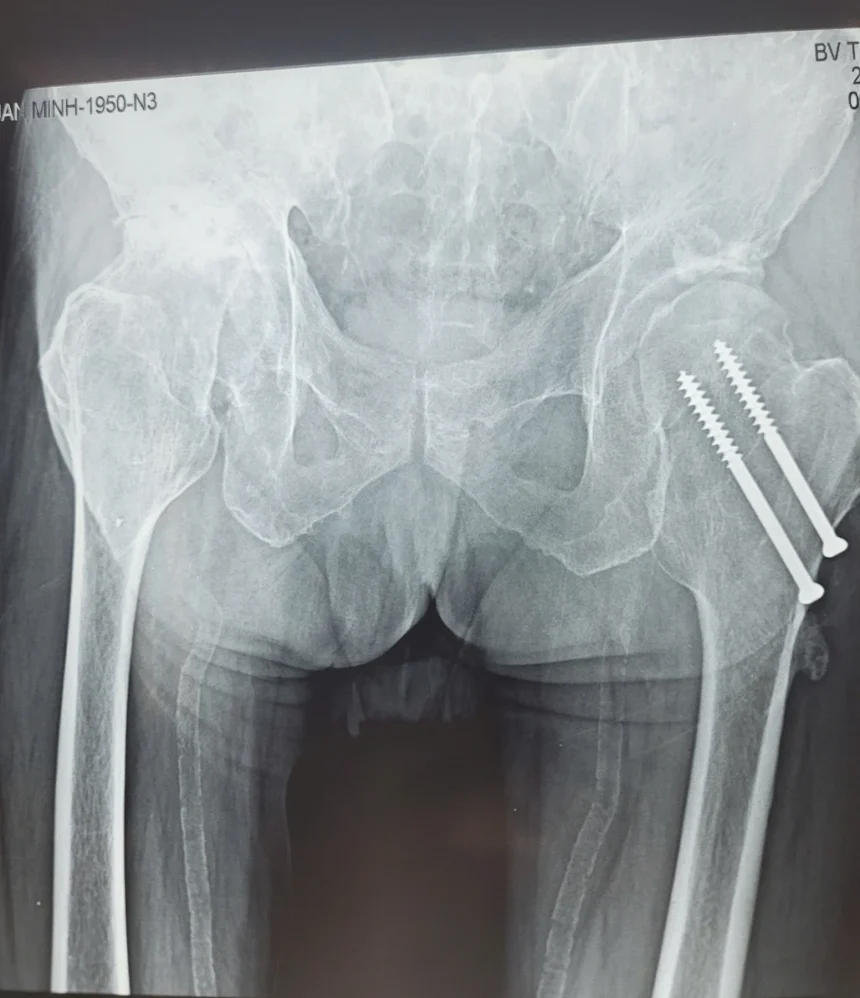

Các bác sĩ phát hiện thêm tình trạng hoại tử chỏm xương đùi phải trên phim X-Quang, gây đau khớp háng và ảnh hưởng nghiêm trọng đến chất lượng cuộc sống của bệnh nhân.

Xray bệnh nhân

Sau khi đánh giá kỹ tình trạng tim mạch ổn định, các bác sĩ đã hội chẩn với chuyên khoa Chấn thương Chỉnh hình và quyết định phẫu thuật thay khớp háng bán phần.

Bệnh nhân Trần Tuấn Minh, nam giới 73 tuổi, có tiền sử bệnh lý tim mạch nặng với các bệnh lý bao gồm: tăng huyết áp, rối loạn lipid máu, đã từng phẫu thuật bắc 3 cầu mạch vành. Đáng chú ý, bệnh nhân có tiền sử gãy cổ xương đùi trái đã được phẫu thuật trước đó.